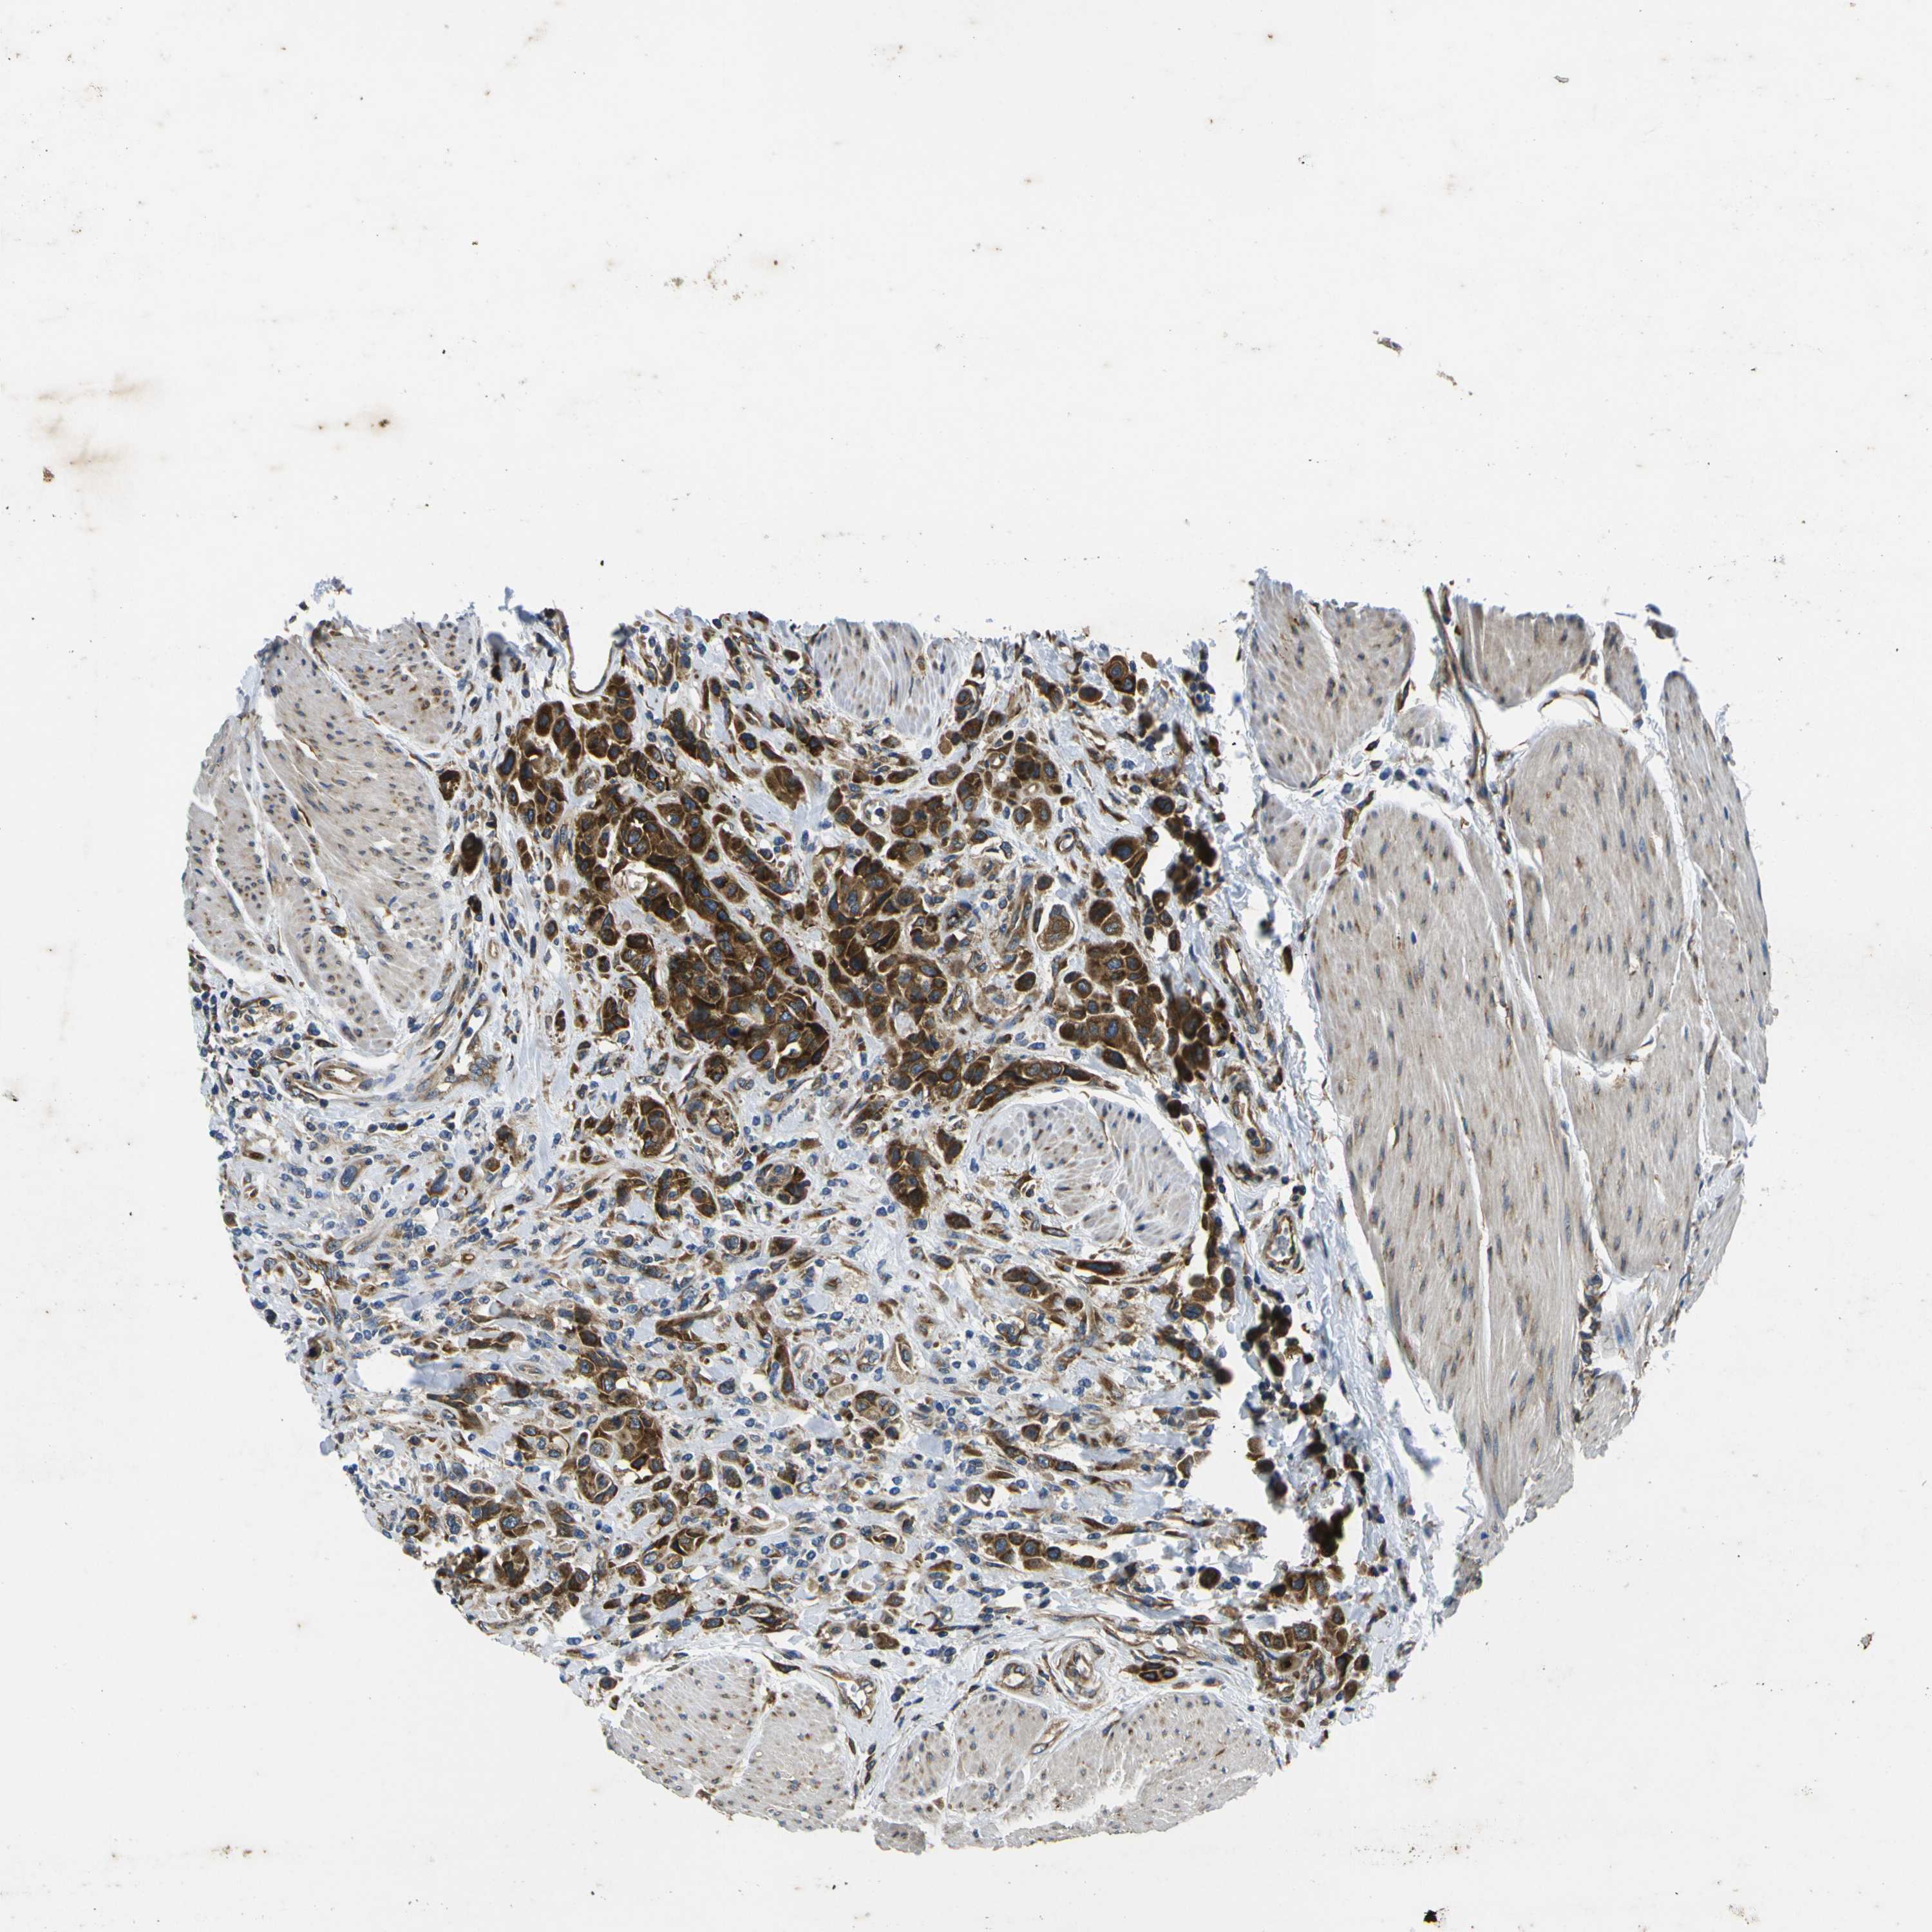

UROTHELIAL CANCER - Protein expressioni

A mouse-over function shows sample information and annotation data. Click on an image to view it in a full screen mode. Samples can be filtered based on level of antibody staining by selecting one or several of the following categories: high, medium, low and not detected. The assay and annotation is described here.

Note that samples used for immunohistochemistry by the Human Protein Atlas do not correspond to samples in the TCGA dataset.

Antibody stainingi

Antibody staining in the annotated cell types in the current human tissue is reported as not detected, low, medium, or high, based on conventional immunohistochemistry profiling in selected tissues. This score is based on the combination of the staining intensity and fraction of stained cells.

Each image is clickable and will lead to virtual microscopy that enables deeper exploration of all samples and also displays staining intensity scores, fraction scores and subcellular localization as well as patient and tissue information for each sample.

Antibody CAB009561

Staining

High

Medium

Low

Not detected

Intensity

Strong

Moderate

Weak

Negative

Quantity

>75%

75%-25%

<25%

None

Location

Nuclear

Cytoplasmic/membranous

Cytoplasmic/membranous,nuclear

Urothelial carcinoma, High grade

Urothelial carcinoma, Low grade